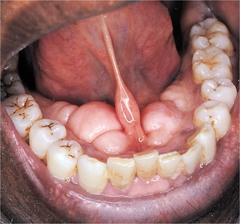

-localized tissue swelling that increases and decreases in size most commonly on lower lip -severed salivary gland duct -mucous filled